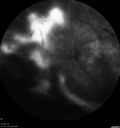

PDR and Vitreous Hemorrhage - High Risk Left Eye - Low Risk Right Eye369 views50 year old man with type I diabetes mellitus for 26 years. New Vitreous Hemorrhage in the left eye. Both eyes have NVE. Both also have foveal hypoplasiaMar 07, 2020

PDR and Vitreous Hemorrhage - High Risk Left Eye - Low Risk Right Eye347 views50 year old man with type I diabetes mellitus for 26 years. New Vitreous Hemorrhage in the left eye. Both eyes have NVE. Both also have foveal hypoplasiaMar 07, 2020

PDR and Vitreous Hemorrhage - High Risk Left Eye - Low Risk Right Eye342 views50 year old man with type I diabetes mellitus for 26 years. New Vitreous Hemorrhage in the left eye. Both eyes have NVE. Both also have foveal hypoplasiaMar 07, 2020

PDR and Vitreous Hemorrhage - High Risk Left Eye - Low Risk Right Eye340 views50 year old man with type I diabetes mellitus for 26 years. New Vitreous Hemorrhage in the left eye. Both eyes have NVE. Both also have foveal hypoplasiaMar 07, 2020

PDR and Vitreous Hemorrhage - High Risk Left Eye - Low Risk Right Eye577 views50 year old man with type I diabetes mellitus for 26 years. New Vitreous Hemorrhage in the left eye. Both eyes have NVE. Both also have foveal hypoplasiaMar 07, 2020

PDR and Vitreous Hemorrhage - High Risk Left Eye - Low Risk Right Eye460 views50 year old man with type I diabetes mellitus for 26 years. New Vitreous Hemorrhage in the left eye. Both eyes have NVE. Both also have foveal hypoplasiaMar 07, 2020

PDR and Vitreous Hemorrhage - High Risk Left Eye - Low Risk Right Eye395 views50 year old man with type I diabetes mellitus for 26 years. New Vitreous Hemorrhage in the left eye. Both eyes have NVE. Both also have foveal hypoplasiaMar 07, 2020

PDR and Vitreous Hemorrhage - High Risk Left Eye - Low Risk Right Eye372 views50 year old man with type I diabetes mellitus for 26 years. New Vitreous Hemorrhage in the left eye. Both eyes have NVE. Both also have foveal hypoplasiaMar 07, 2020

PDR and Vitreous Hemorrhage - High Risk Left Eye - Low Risk Right Eye360 views50 year old man with type I diabetes mellitus for 26 years. New Vitreous Hemorrhage in the left eye. Both eyes have NVE. Both also have foveal hypoplasiaMar 07, 2020

PDR and Vitreous Hemorrhage - High Risk Left Eye - Low Risk Right Eye397 views50 year old man with type I diabetes mellitus for 26 years. New Vitreous Hemorrhage in the left eye. Both eyes have NVE. Both also have foveal hypoplasiaMar 07, 2020

PDR and Vitreous Hemorrhage - High Risk Left Eye - Low Risk Right Eye398 views50 year old man with type I diabetes mellitus for 26 years. New Vitreous Hemorrhage in the left eye. Both eyes have NVE. Both also have foveal hypoplasiaMar 07, 2020

PDR and Vitreous Hemorrhage - High Risk Left Eye - Low Risk Right Eye338 views50 year old man with type I diabetes mellitus for 26 years. New Vitreous Hemorrhage in the left eye. Both eyes have NVE. Both also have foveal hypoplasiaMar 07, 2020

PDR and Vitreous Hemorrhage - High Risk Left Eye - Low Risk Right Eye351 views50 year old man with type I diabetes mellitus for 26 years. New Vitreous Hemorrhage in the left eye. Both eyes have NVE. Both also have foveal hypoplasiaMar 07, 2020

PDR and Vitreous Hemorrhage - High Risk Left Eye - Low Risk Right Eye335 views50 year old man with type I diabetes mellitus for 26 years. New Vitreous Hemorrhage in the left eye. Both eyes have NVE. Both also have foveal hypoplasiaMar 07, 2020

PDR and Vitreous Hemorrhage - High Risk Left Eye - Low Risk Right Eye402 views50 year old man with type I diabetes mellitus for 26 years. New Vitreous Hemorrhage in the left eye. Both eyes have NVE. Both also have foveal hypoplasiaMar 07, 2020

PDR and Vitreous Hemorrhage - High Risk Left Eye - Low Risk Right Eye325 views50 year old man with type I diabetes mellitus for 26 years. New Vitreous Hemorrhage in the left eye. Both eyes have NVE. Both also have foveal hypoplasiaMar 07, 2020

PDR and Vitreous Hemorrhage - High Risk Left Eye - Low Risk Right Eye343 views50 year old man with type I diabetes mellitus for 26 years. New Vitreous Hemorrhage in the left eye. Both eyes have NVE. Both also have foveal hypoplasiaMar 07, 2020

PDR and Vitreous Hemorrhage - High Risk Left Eye - Low Risk Right Eye329 views50 year old man with type I diabetes mellitus for 26 years. New Vitreous Hemorrhage in the left eye. Both eyes have NVE. Both also have foveal hypoplasiaMar 07, 2020

PDR and Vitreous Hemorrhage - High Risk Left Eye - Low Risk Right Eye413 views50 year old man with type I diabetes mellitus for 26 years. New Vitreous Hemorrhage in the left eye. Both eyes have NVE. Both also have foveal hypoplasiaMar 07, 2020

PDR and Vitreous Hemorrhage - High Risk Left Eye - Low Risk Right Eye312 views50 year old man with type I diabetes mellitus for 26 years. New Vitreous Hemorrhage in the left eye. Both eyes have NVE. Both also have foveal hypoplasiaMar 07, 2020

PDR and Vitreous Hemorrhage - High Risk Left Eye - Low Risk Right Eye353 views50 year old man with type I diabetes mellitus for 26 years. New Vitreous Hemorrhage in the left eye. Both eyes have NVE. Both also have foveal hypoplasiaMar 07, 2020

PDR and Vitreous Hemorrhage - High Risk Left Eye - Low Risk Right Eye331 views50 year old man with type I diabetes mellitus for 26 years. New Vitreous Hemorrhage in the left eye. Both eyes have NVE. Both also have foveal hypoplasiaMar 07, 2020

PDR and Vitreous Hemorrhage - High Risk Left Eye - Low Risk Right Eye373 views50 year old man with type I diabetes mellitus for 26 years. New Vitreous Hemorrhage in the left eye. Both eyes have NVE. Both also have foveal hypoplasiaMar 07, 2020

PDR and Vitreous Hemorrhage - High Risk Left Eye - Low Risk Right Eye368 views50 year old man with type I diabetes mellitus for 26 years. New Vitreous Hemorrhage in the left eye. Both eyes have NVE. Both also have foveal hypoplasiaMar 07, 2020

PDR and Vitreous Hemorrhage - High Risk Left Eye - Low Risk Right Eye412 views50 year old man with type I diabetes mellitus for 26 years. New Vitreous Hemorrhage in the left eye. Both eyes have NVE. Both also have foveal hypoplasiaMar 07, 2020